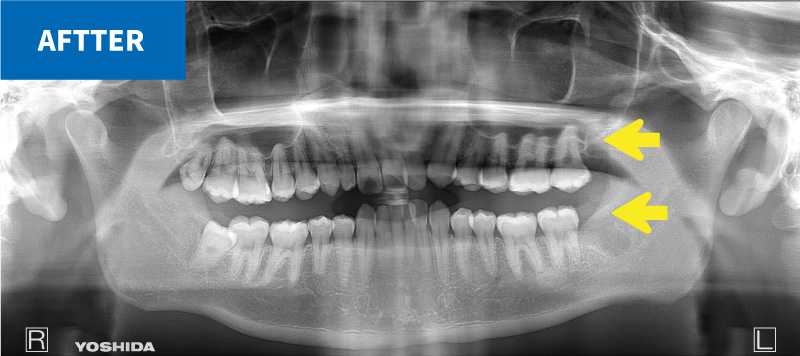

上の親知らずには、歯並びと逸脱した方向に生えてしまうものが多くあります。

これらは、咬み合わせに悪影響を及ぼすだけでなく、周囲の歯の虫歯や歯周病の原因となってしまうことがあります。

これらを安全に抜歯することも口腔外科の仕事です。